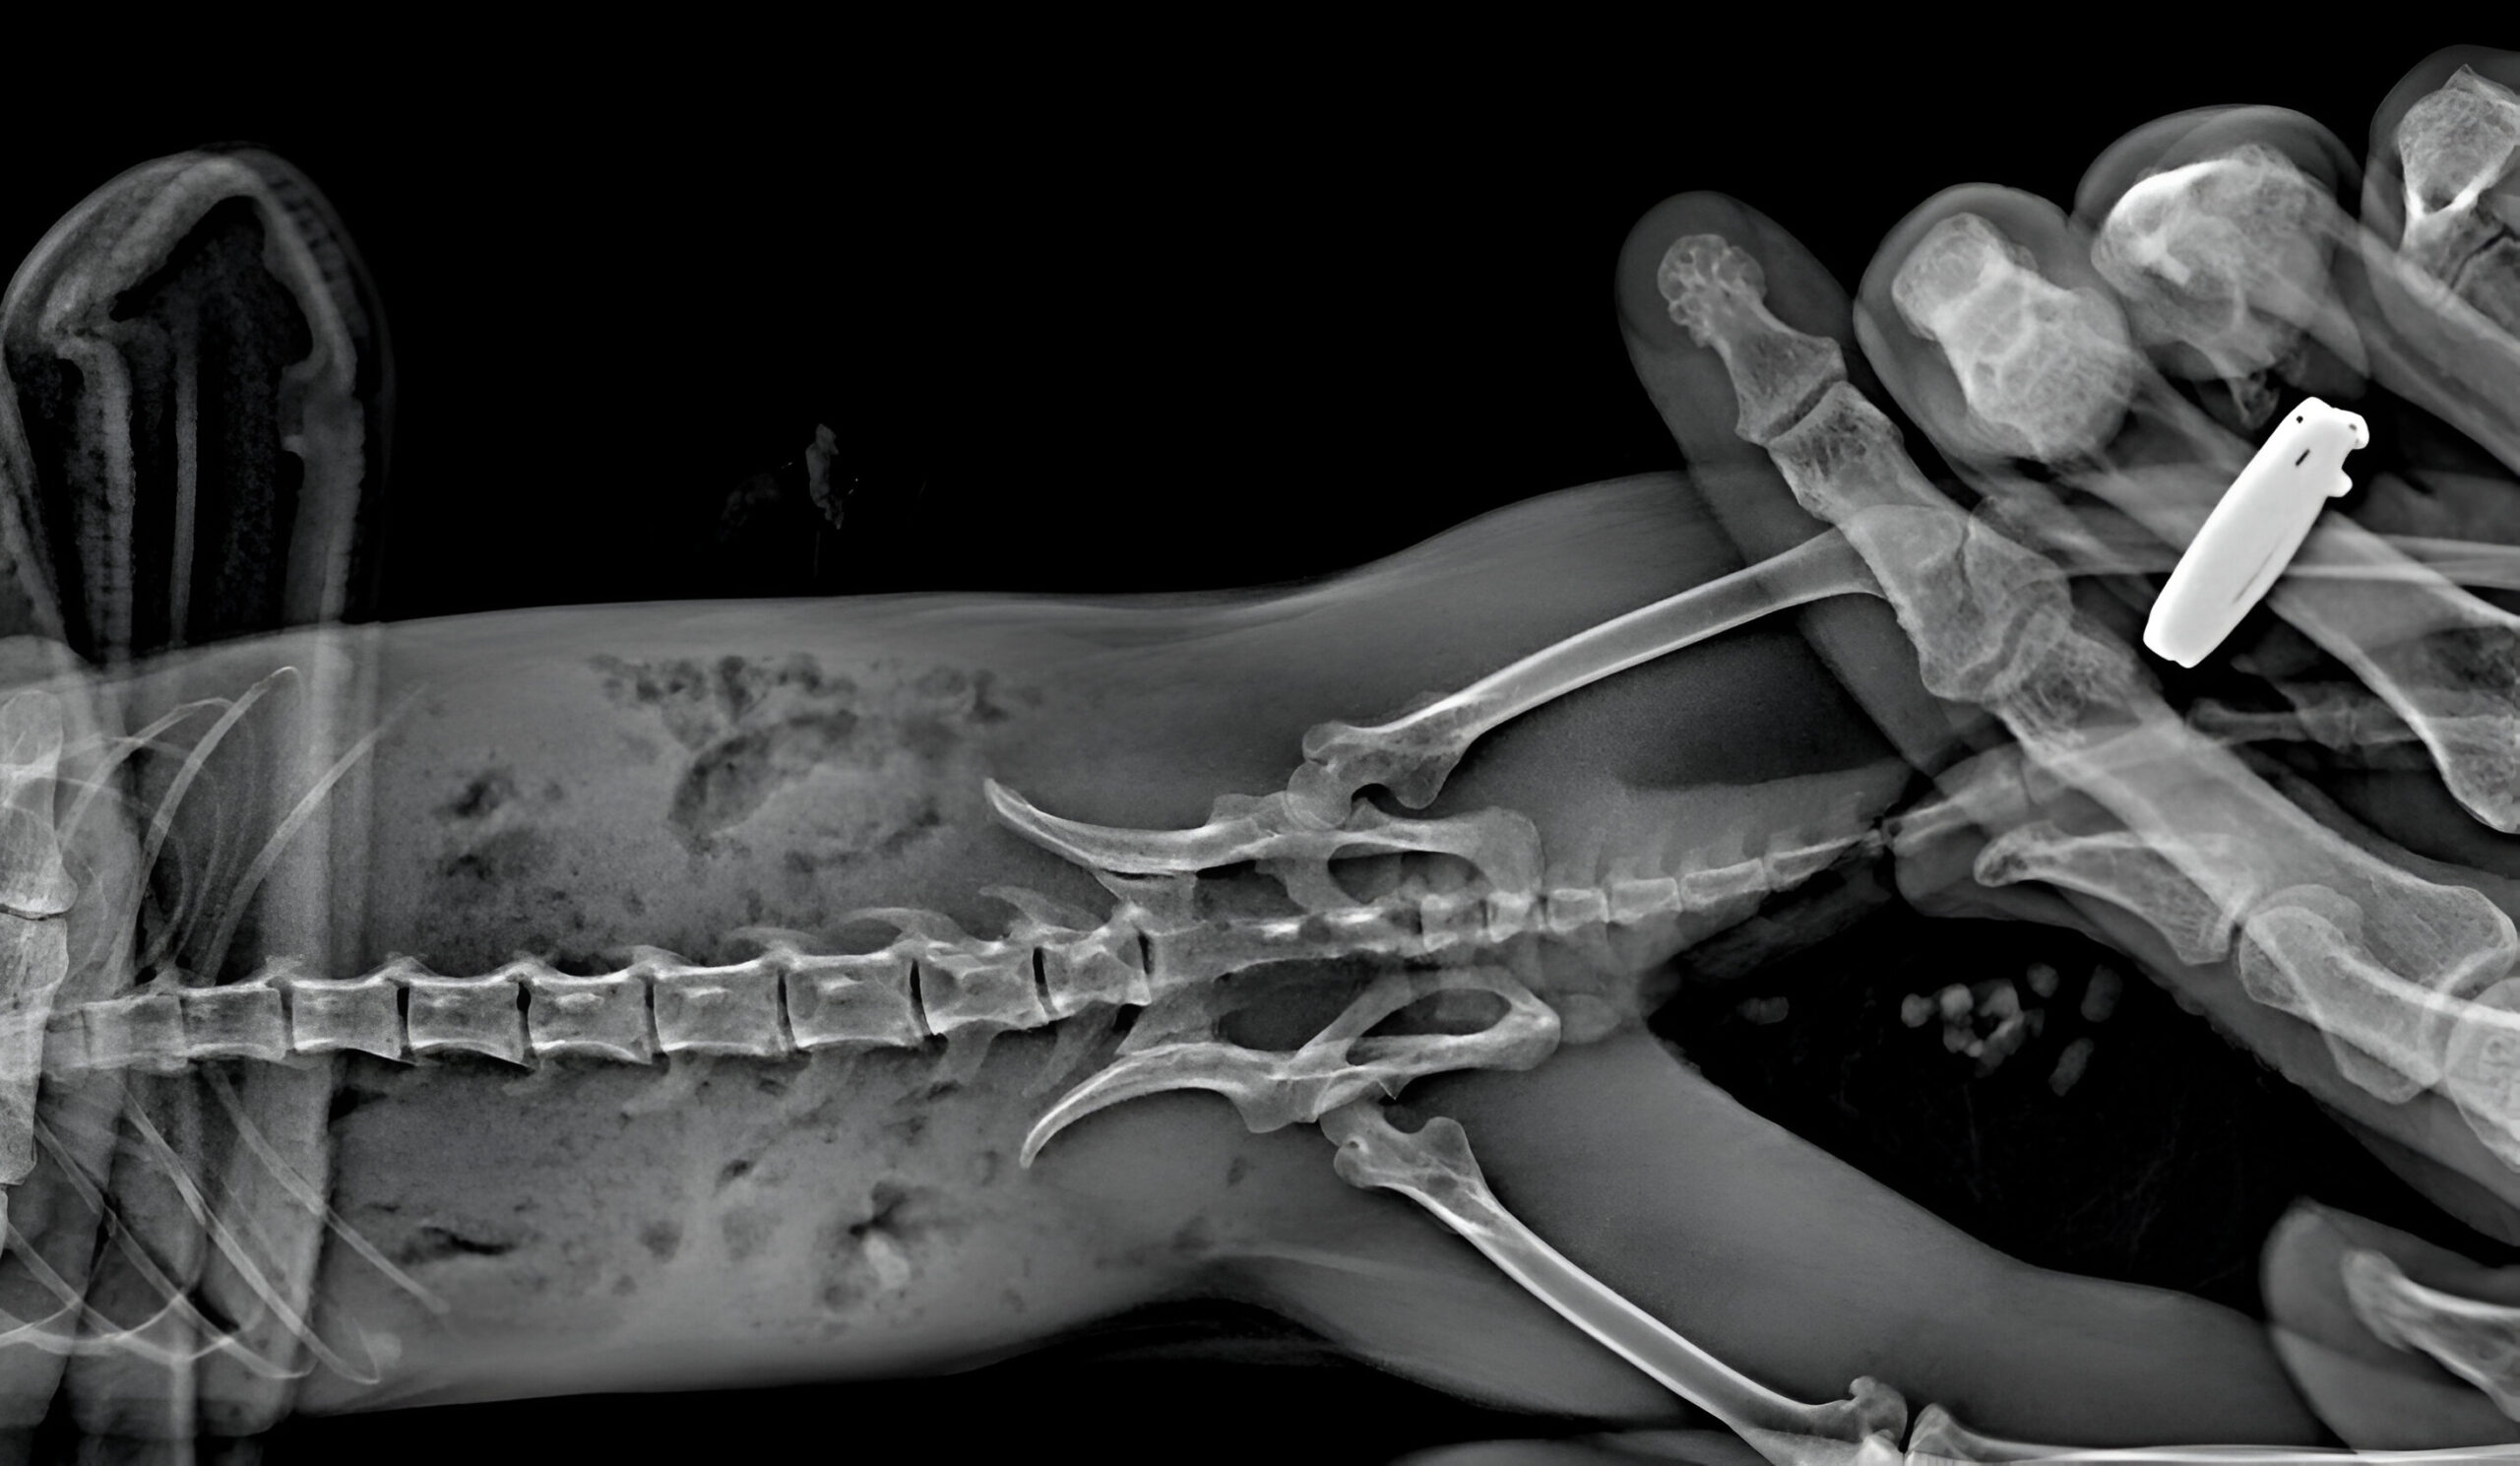

На рентгене выяснили, что у Миланы компрессионный перелом позвоночника — для белки смертельный из-за пережима спинного мозга и отказа задних конечностей. Доктор Васин сказал, что если Милана не сможет сама ходить в туалет — скорее всего, погибнет.